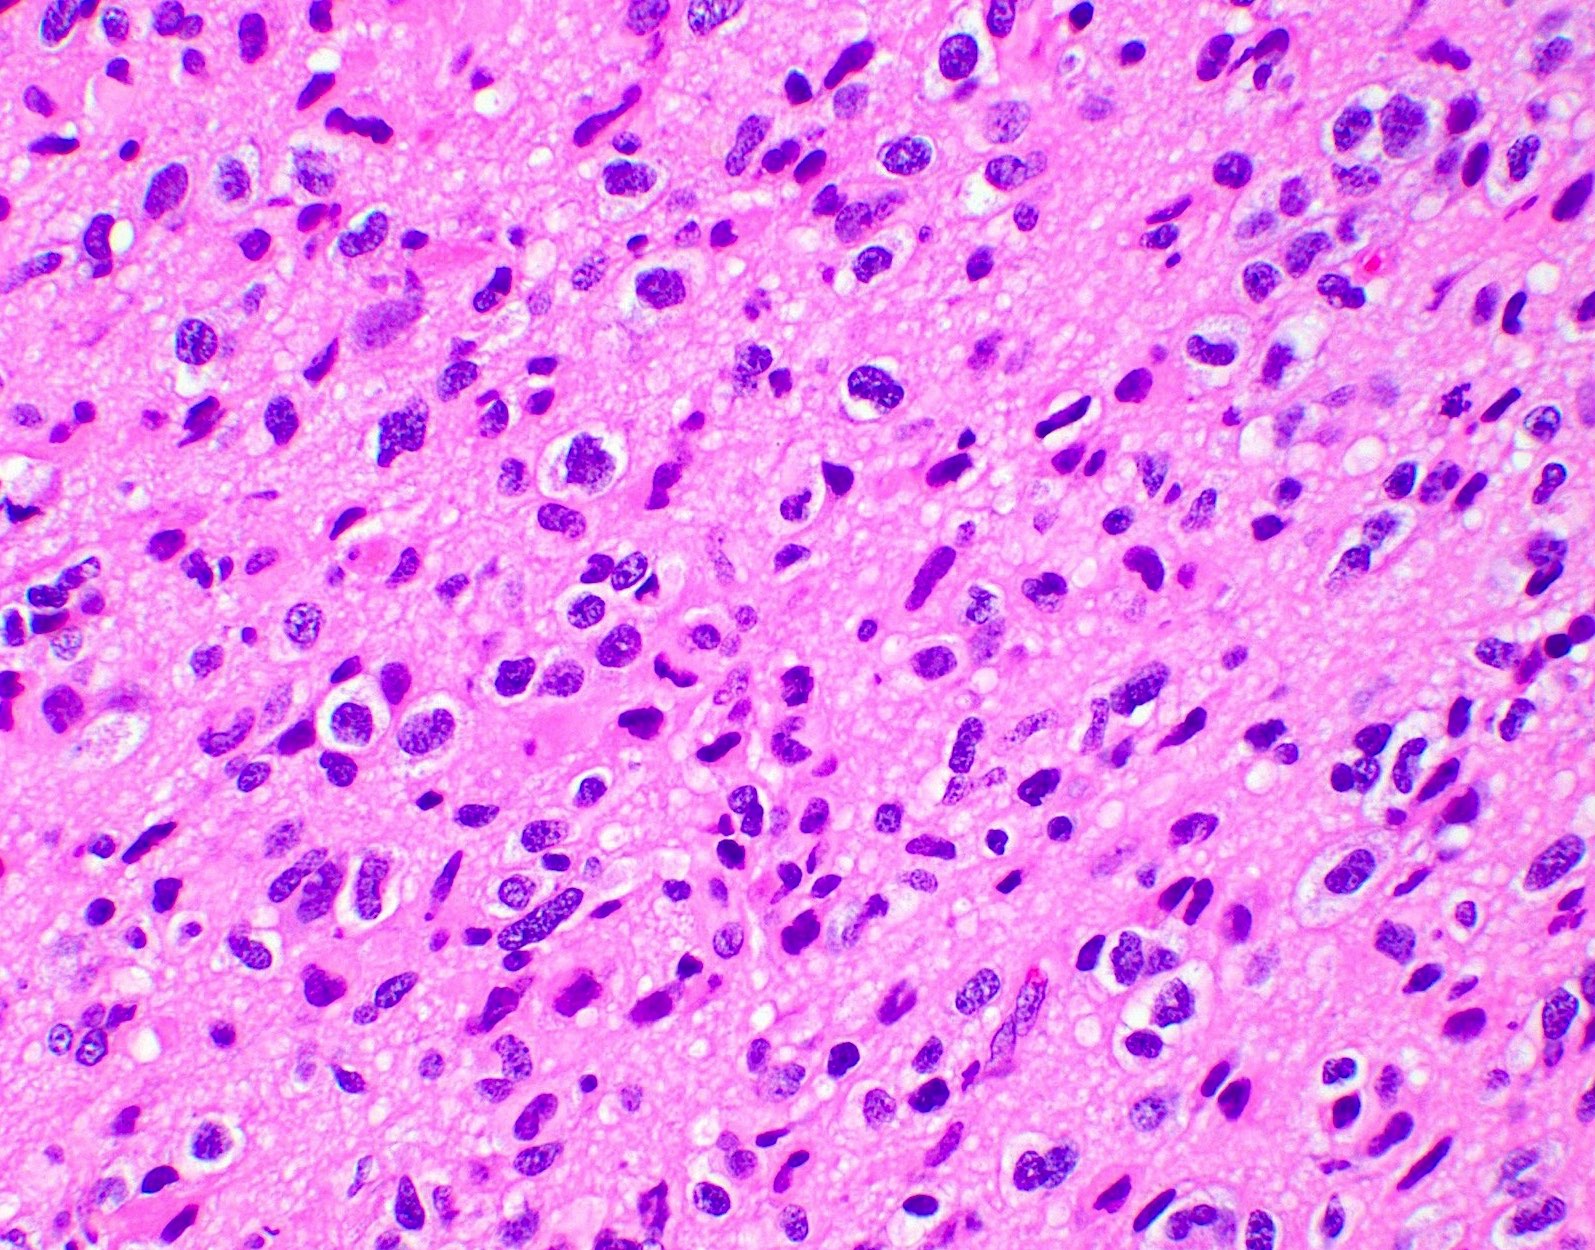

Microscopic (histologic) description

- Closely packed cells with small, round, monotonous nuclei (slightly larger than a normal oligodendrocyte)

- Perinuclear clearing (fried egg appearance)

- Formalin fixation artifact

- Will not be seen on frozen sections or smear preparations

- Network of thin walled, branching blood vessels (chicken wire vasculature)

- Microcalcifications (calcospherites) are characteristic

- Presence of perineural, perivascular or subpial aggregates of tumor cells (secondary structures of Scherer)

- Occasional mitoses and moderate nuclear atypia are still consistent with grade 2 designation (J Neuropathol Exp Neurol 2001;60:248)

- Not uncommon to find well differentiated / fibrillary astrocytic morphology (Acta Neuropathol 1984;64:265)

- Features of CNS WHO grade 3 oligodendroglioma:

- Presence of microvascular proliferation

- Presence of necrosis

- Presence of brisk mitotic activity

- Strict mitotic figure cutoffs do not currently exist; some authors suggest ≥ 6 mitoses per 10 high power fields for WHO grade 3 designation in tumors without necrosis or vascular proliferation (Neuro Oncol 2014;16:1244, Neuro Oncol 2016;18:888)

Microscopic (histologic) images

Contributed by Jared T. Ahrendsen, M.D., Ph.D. and John DeWitt, M.D., Ph.D.

A 42 year old man presents to the emergency room with new onset seizures. Brain magnetic resonance imaging (MRI) reveals a nonenhancing infiltrative mass lesion in the right frontal lobe. A biopsy is performed, shown in the image above. What molecular features are most likely present?

C. IDH mutation and 1p / 19q codeletion. The image shows an oligodendroglioma, which is defined by the presence of IDH mutation and 1p / 19q codeletion.